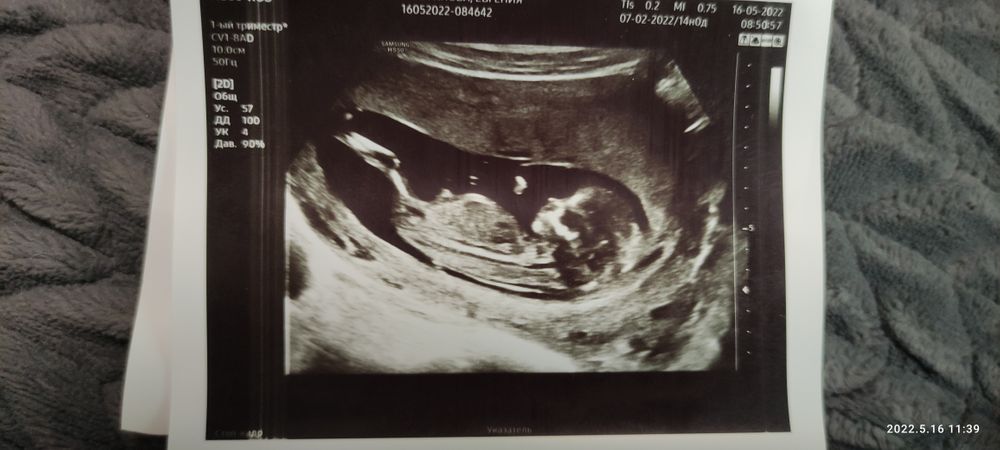

Думаю мальчик, по форме головки так кажется

Тоже думаю мальчик, где-то читала, что пузатенькие мальчики) у меня пока так и есть, перепроверим через несколько недель

Не спрашивайте почему, мальчик 💙

Не видно половой бугорок - закрыт ножкой.

Тут не понятно, да и рано)

Девочка думаю, торчит возле попы отросточек, а сверху это пуповина🙂

Мне кажется мальчик . А мне зачем то 3Д сегодня показали ,там вообще ничего не понятно ,где голова ,где ноги. В чб варианте красивее малыши смотреться на этом сроке .

Мне кажется девочка